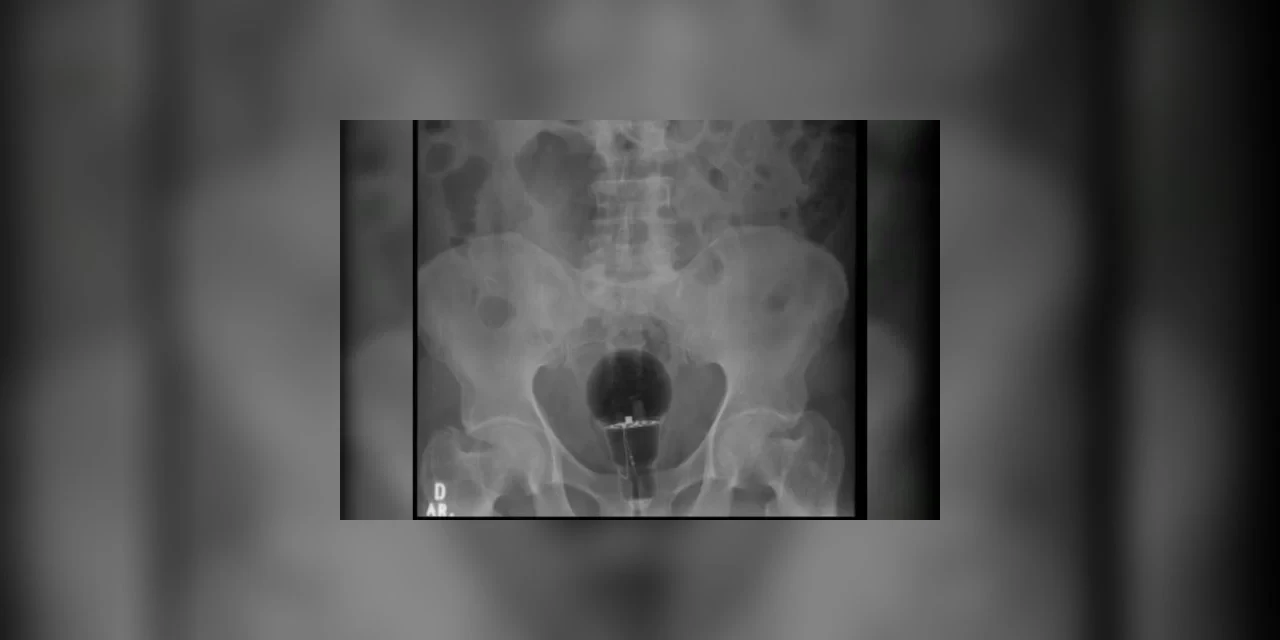

Paciente passa por procedimento para retirar lâmpada do ânus

Foto: Reprodução

Um homem colombiano de 53 anos chegou a um hospital do país com dores intensas em março último. Aos médicos, o paciente disse não saber do que se tratava. No entanto, exames de imagem mostraram que uma lâmpada foi enfiada em seu reto. “O objeto não era palpável ao toque”, afirmou o gastroenterologista Julian Pylori, que fez o atendimento, em um tweet. O médico usa as redes sociais com frequência para compartilhar atendimentos inusitados. Perigo Objetos como este, que correm o risco de se quebrar, tem de ser retirados do corpo em procedimentos cirúrgicos. No entanto, segundo reportagem da TV Azteca, foi possível succionar a lâmpada porque ela era feita de plástico. O homem sofria com dores há três dias e não havia ido ao hospital antes por medo de que sua esposa soubesse do acidente.